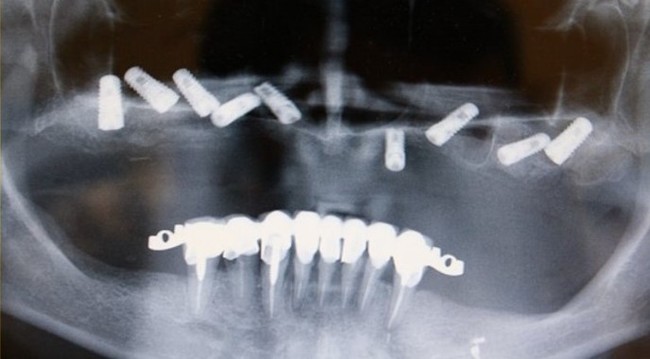

На панорамном снимке ниже по середине четко видны контрастные «белые цилиндры», это как раз и есть тот самый материал, которым были закрыты отверстия в верхнем съемном протезе. Сам протез не рентгеноконтрастен, поэтому его на снимке не видно.

Ну и на десерт. Узрите! Вот оно, ТВАРЬение! Об этом я и говорил, пластиночный имплантат с отверстиями в нем, в которые проросла костная ткань. Ну и сломанный «штырь», который был одной из опор для мостовидного протеза.